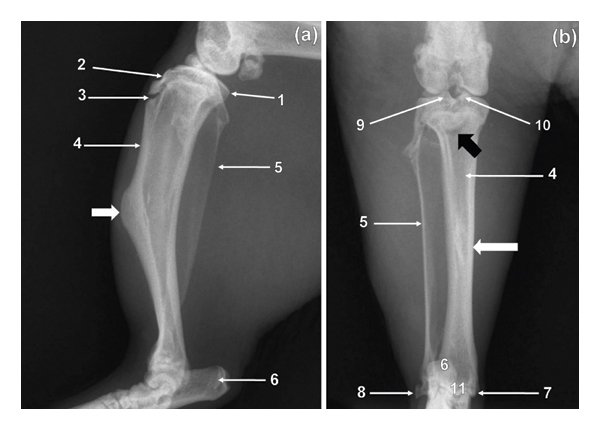

3.3. Tibia and Fibula

The two bones were unfused in all specimens (Figure 3). The tibia was larger compared to fibula (Figure 3). The former was wider craniocaudally and flattened mediolaterally (Figure 3). The condyles of the tibia were wider than the cochlea of the tibia (Figure 3(b)). The fibula was wider craniocaudally and narrower mediolaterally (Figure 3). The craniocaudal width of the bone decreased from proximal to distal (Figure 3). The tibial tuberosity was less conspicuous, whereas the intercondylar eminence remained conspicuous on the ML view (Figure 3(a)). The tibia bent cranially on its longitudinal axis (Figure 3(a)) and presented a very prominent tuberosity (Figure 3(a)) on its cranial surface at the middle third of the body. Cranial cortex of the tibia was thicker than the caudal cortex (Figure 3(a)). The fibula was wide with its proximal and distal extremities superimposed on the proximal and distal extremities, respectively, of the tibia (Figure 3(a)). On the CdCr view, the tibia appeared fairly straight (Figure 3(b)). The intercondylar tubercles were prominent and of almost of the same height (Figure 3(b)). Proximal extremity of the tibia presented a crescent-shaped radiolucent area which corresponded to the physis of the tibial tuberosity (Figure 3(b)). Increased area of bone opacity was visualised in the middle third of the body of the tibia (Figure 3(b)) as a result of the presence of the very prominent tuberosity (Figure 3(a)). The lateral malleolus of the fibula appeared comma shaped whereas the medial malleolus of the tibia was short and directed distally (Figure 3(b)).